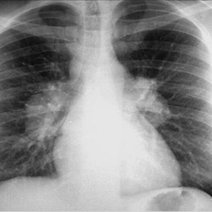

[最佳答案] IgG4相关疾病是一种自身免疫病。这种病主要是由于炎性纤维化,可以造成多个器官和系统的器官肿大组织破坏,甚至是器官功能衰竭。由于这种疾病血清当中的IgG4水平升高,所以以此命名。这类疾病通常会有1个或多个器官肿大。病理学会显示有淋巴细胞和浆细胞的浸润以及纤维化。治疗上以激素治疗为主,同时可以加用免疫抑制剂,比如硫唑嘌呤,吗替麦考酚酯,环磷酰胺等等。